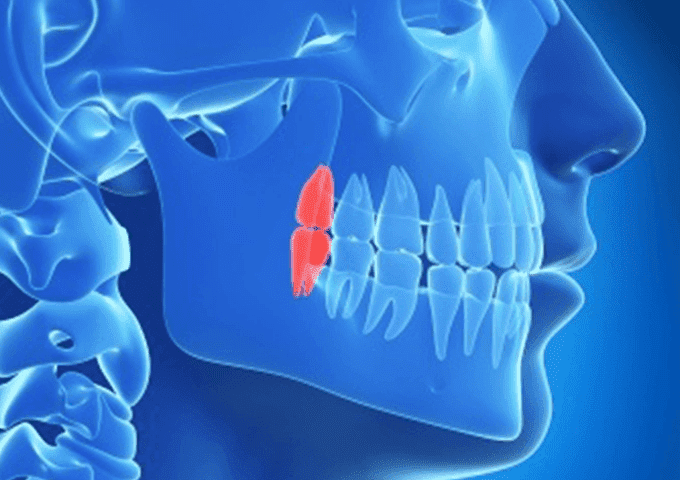

顎の骨の深い部分に埋まった状態の親知らずは、傾いた状態や横を向いた状態のものもあります。

これらの親知らずは、本来抜歯が非常に難しいのですが、三次元の画像で事前に確認することで安全かつ精度の高い治療を行うことが出来ます。

そのため、難抜歯であっても短時間で治療を行える確率が高くなり、患者様の負担も軽減されることとなります。